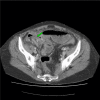

Acute appendicitis is a common surgical problem however the diagnosis is often overlooked when it presents as a small bowel obstruction. In this report we present two cases of elderly patients who presented with small bowel obstruction and raised inflammatory markers. Both patients were successfully treated with a laparotomy, adhesiolysis and appendicectomy and went on to make a good recovery.